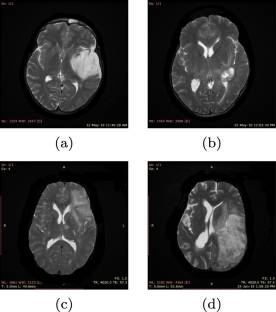

Computer aided diagnosis using artificial intelligent techniques made tremendous improvement in medical applications especially for easy detection of tumor area, tumor type and grades. This paper presents automatic glioma tumor grade identification from magnetic resonant images using Wndchrm tool based classifier (Weighted Neighbour Distance using Compound Heirarchy of Algorithms Representing Morphology) and VGG-19 deep convolutional neural network (DNN). For experimentation, DICOM images are collected from reputed government hospital and the proposed intelligent system categorized the tumor into four grades such as low grade glioma, oligodendroglioma, anaplastic glioma and glioblastoma multiform. After preprocessing, features are extracted, optimized and then classified using Windchrm tool where the most significant features are selected on the basis of Fisher score. In the case of DNN classifier, data augmentation is also performed before applying the images into the deep learning network. The performance of the classifiers are analysed with various measures such as accuracy, precision, sensitivity, specificity and F1-score. The results showed reasonably good performance with a maximum classification accuracy of 92.86% for the Wndchrm classifier and 98.25% for VGG-19 DNN classifier. The results are also compared with similar recent works and the proposed system is found to have better performance.

Fig. 1

Fig. 2

Fig. 3

Fig. 4